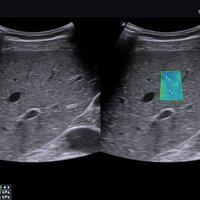

Das X-CUBE 70 bietet modernste Technologien für eine objektive und akkurate Diagnose. Intelligente klinische Module heben das System auf ein neues diagnostisches Niveau. Es erweitert Ihre Fähigkeiten und die Bandbreite Ihrer Möglichkeiten. Dazu gehören Module wie MicroView, point Shear Wave Elastographie (pSWE), oder auch die Kontrastmittelsonographie.

• X+ Architecture mit Parallel-Beamforming für erhöhte Auflösung, Bildrate und Penetration